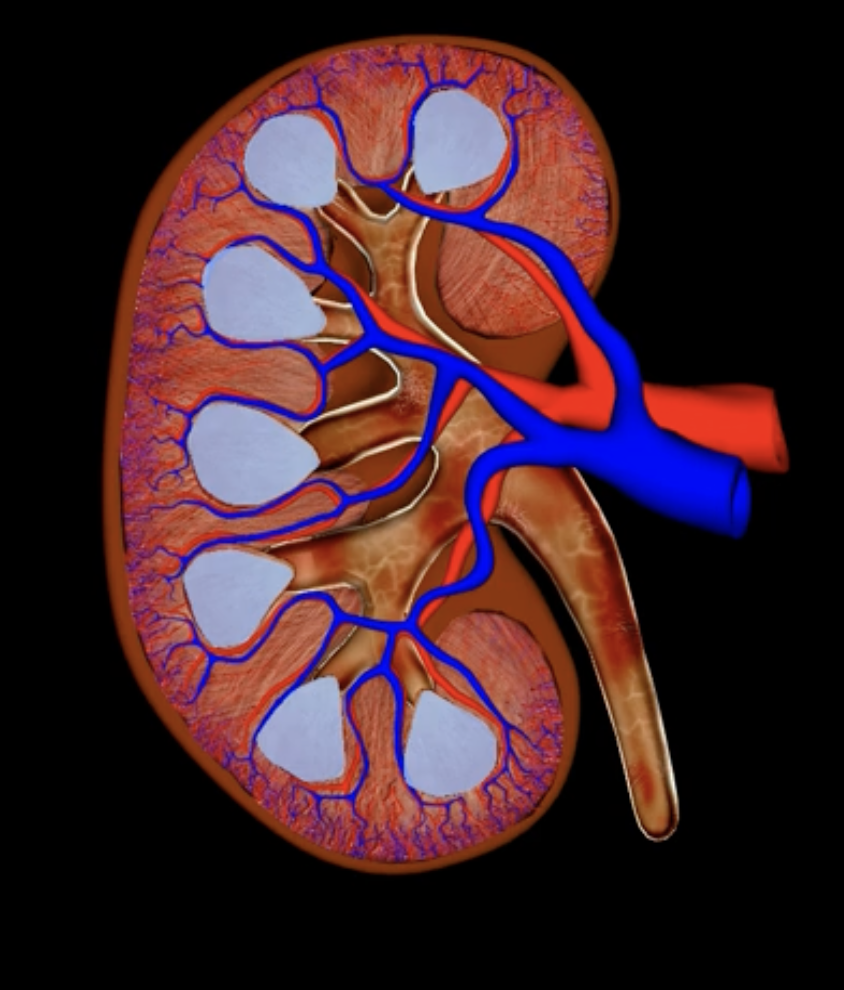

renal cortex

green

renal medulla

blue

renal columns

yellow

renal pyramids

purple

renal lobe

orange

renal papilla

minor calyx

teal

major calyces

renal pelvis